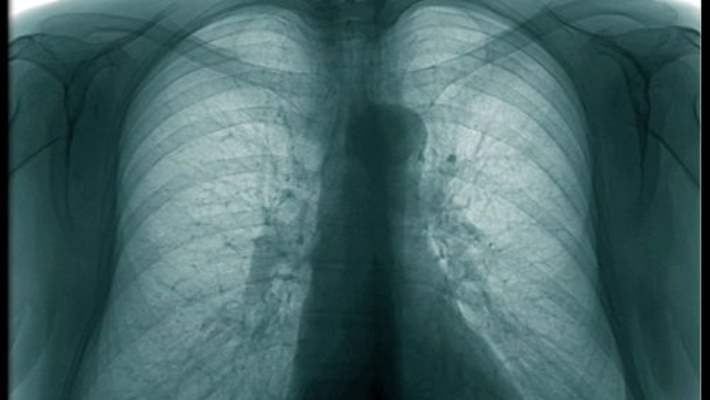

Akciğer Embolisinin Belirtileri Nelerdir?